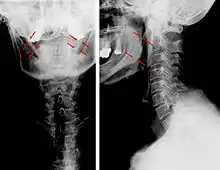

CT scan, coronal section showing bilateral extended styloid process and stylohyoid ligament ossification (incidental finding)

Diagnosis is suspected when a patient presents with the symptoms of the classic form of "Eagle syndrome" e.g. unilateral neck pain, sore throat or tinnitus. Sometimes the tip of the styloid process is palpable in the back of the throat. The diagnosis of the vascular type is more difficult and requires an expert opinion. One should have a high level of suspicion when neurological symptoms occur upon head rotation. Symptoms tend to be worsened on bimanual palpation of the styloid through the tonsillar bed. They may be relieved by infiltration of lidocaine into the tonsillar bed. Because of the proximity of several large vascular structures in this area this procedure should not be considered to be risk free.

Imaging is important and is diagnostic. Visualizing the styloid process on a CT scan with 3D reconstruction is the suggested imaging technique.[13] The enlarged styloid may be visible on an orthopantogram or a lateral soft tissue X ray of the neck.